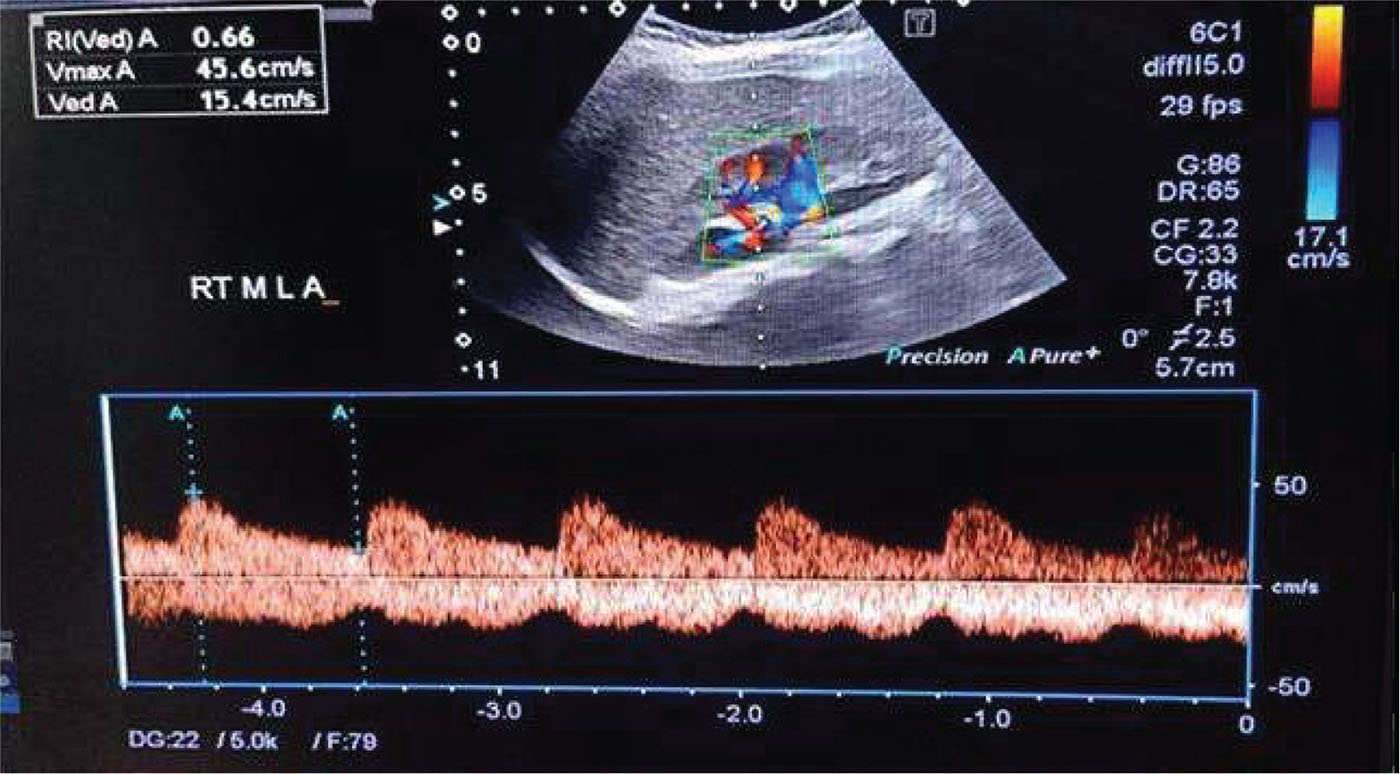

Renal Doppler ultrasound evaluation was done in the lateral oblique position or oblique position; however, the left kidney was better examined in a right lateral decubitus. The examination was done using Philips 50G ultrasound machine with low-frequency convex probe (5 MHz) (Fig. 2). Firstly, both kidneys were scanned using B mode for detection of any gross abnormalities such as stones, backpressure changes, echogenicity, cortical thickness or focal lesions. Color Doppler was applied to see interlobar arteries, and then the sample volume was applied to cover only the arterial diameter of interest. Optimum waveform was obtained by adjustment of both the pulse repetition frequency (PRF) and the wall filter to avoid aliasing. Measurement of Doppler parameters was taken at breath holds in cooperative children and in younger children at quiet respiration. For each kidney, RIs of renal interlobar arteries at the upper, middle and lower poles were assessed three times, then the average of the measurements was taken. The arterial RI was calculated by the equation (peak systolic velocity − end diastolic velocity) divided by (peak systolic velocity), and its value is derived via the computer algorithm in the ultrasound machine.

FIGURE 2 - Color duplex ultrasound measurements of the right and middle pole interlobar artery resistive index.